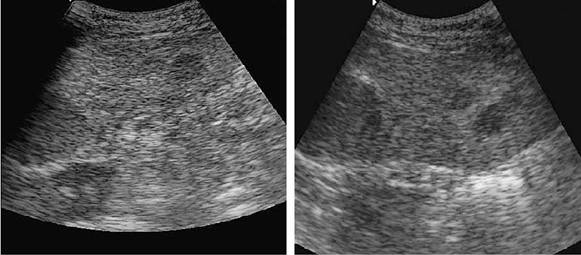

Figura 21-2. Ultra-sonografia do baço, na qual se observam áreas hipoecóicas arredondadas de tamanhos variados.